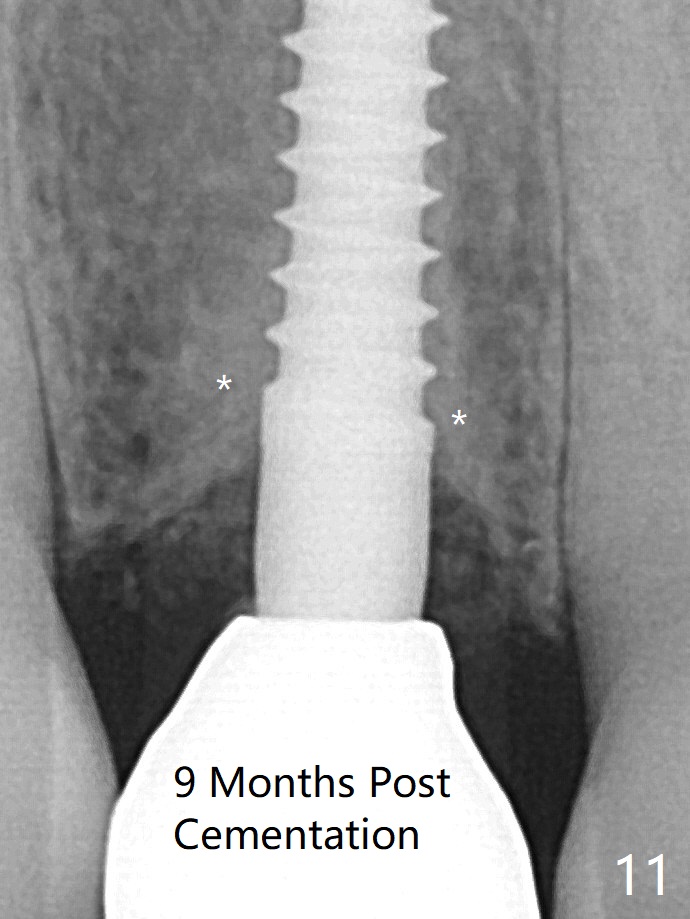

After adjustment of the trajectory of osteotomy (Fig.5), a 3x16(2) mm 1-piece implant is placed within normal limit (10-15 Ncm, Fig.6)). In fact bone graft is placed before (^ arrowhead; to repair apical buccal plate perforation) and after (*) implantation. The bone graft becomes more organized 3 months postop (Fig.9), continues to do so 4.5 months postop (Fig.10) and becomes dense 9 months coronally post cementation (Fig.11: *). 牙冠粘固后九个月(术后一年)骨粉密度增加(图十一)。